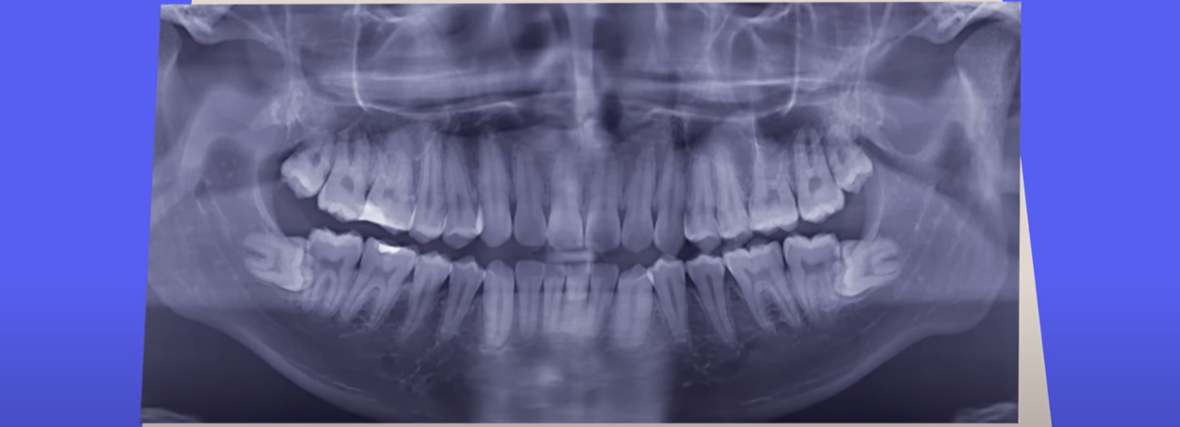

Waarom hebben we nog verstandskiezen?

Dat onder andere verstandskiezen verdwijnen, heeft alles te maken met evolutie: als iets niet meer nuttig is, dan kan het in de loop van de tijd verdwijnen. Braumuller onderzoekt dit fenomeen bij mensen en dieren. 'Het heeft eigenlijk altijd te maken met een omgeving die aan het veranderen is.'